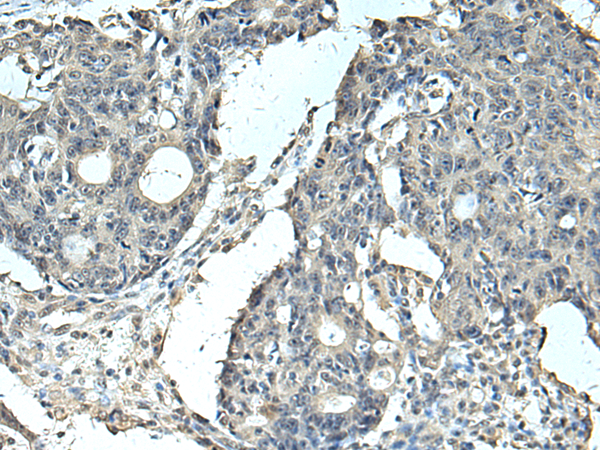

IHC positive control: |

Human colorectal cancer and Human tonsil |

IHC Recommend dilution: |

100-300 |